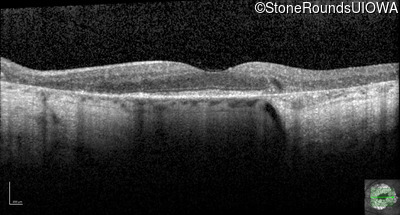

Age at visit: 59 years

This 59 year old woman first experienced defects in her mid peripheral field in the past year. Her hearing worsened in her 30's and she started wearing hearing aids at age 40. She was diagnosed with diabetes at age 39 and began using insulin at age 42.